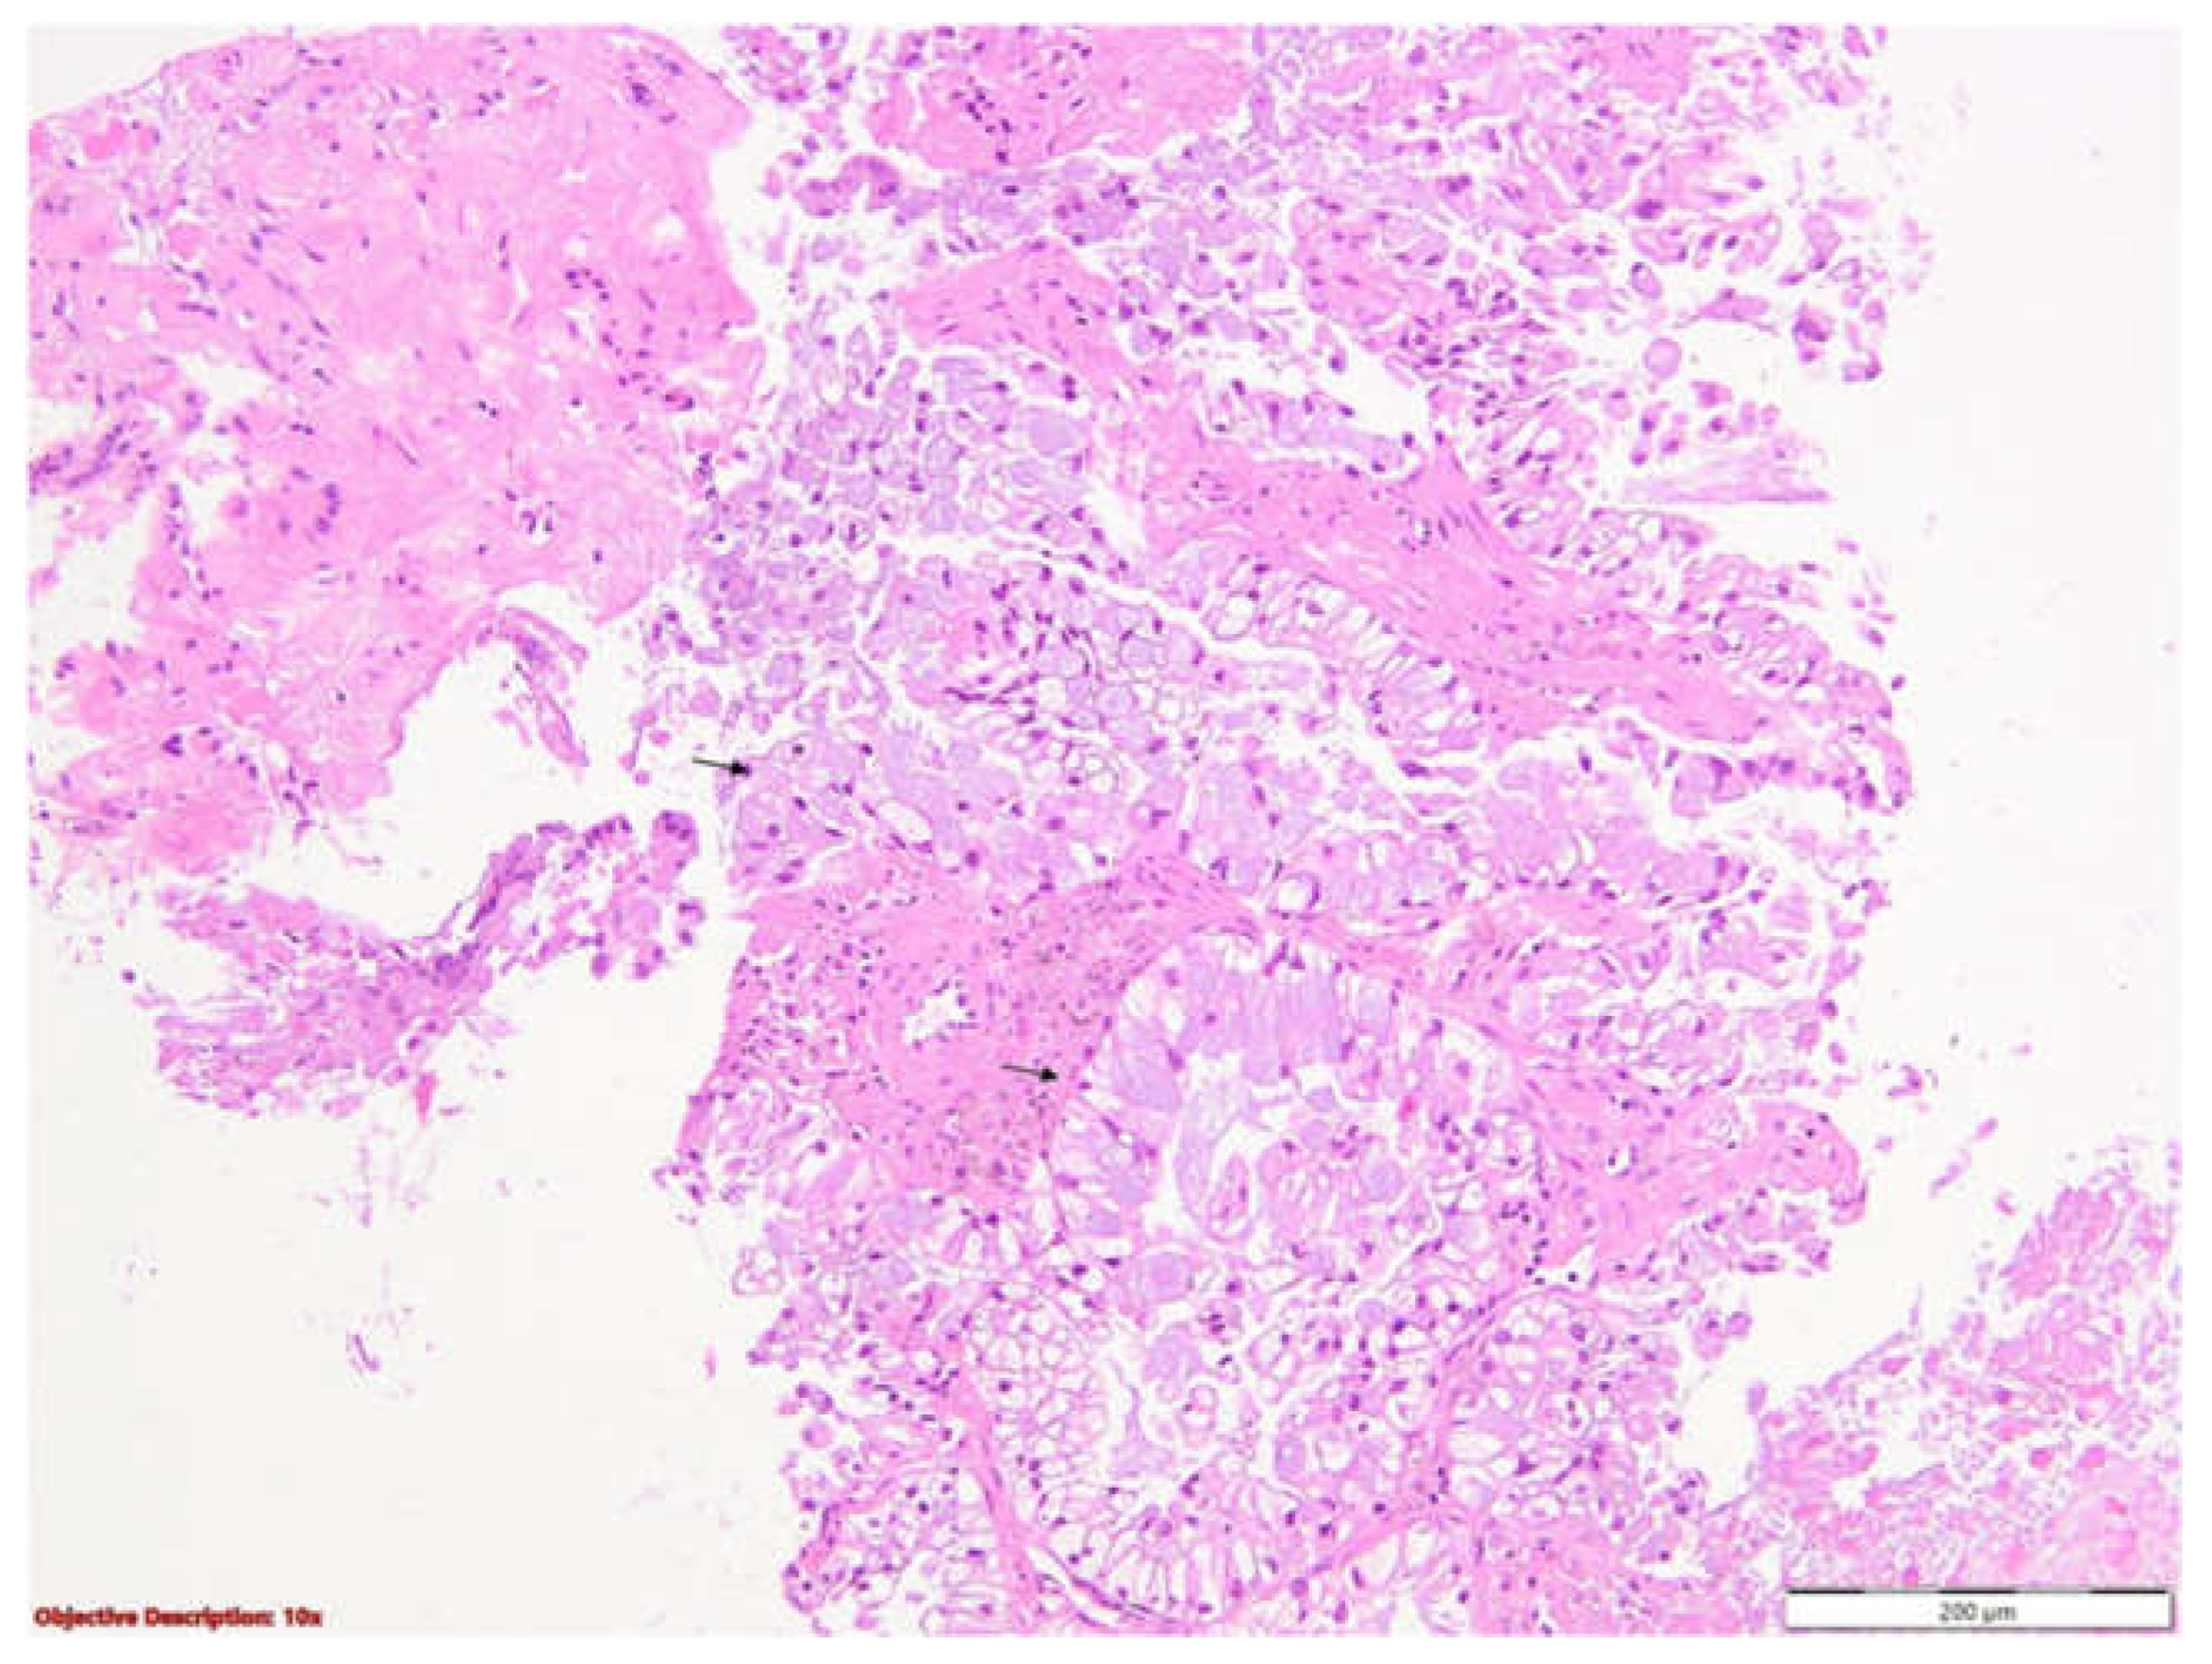

To clarify the etiology of the pleural abnormalities identified on imaging, a thoracic surgery consultation was obtained, followed by an ultrasound-guided right pleural biopsy. A histopathological examination (Figure 4 and Figure 5) revealed carcinomatous infiltrates with a solid and tubular architecture, composed of atypical cylindrical epithelial cells with mucin secretion. These findings were consistent with a parietal tumor mass, suggestive of adenocarcinoma of an uncertain primary origin, most likely pulmonary. Subsequent immunohistochemical profiling confirmed the diagnosis of invasive pulmonary adenocarcinoma, displaying a predominantly acinar pattern with focal solid components.

A bronchoscopy was also performed. An examination of the right bronchial tree revealed a normal configuration of the right main bronchus. The spur of the right upper lobe bronchus appeared slightly widened, while the intersegmental spurs of the right upper lobe (RUL) were prominent, with visibly congested mucosa. The anterior segment of the RUL demonstrated approximately 50% luminal narrowing, which impeded further advancement of the bronchoscope at this level. A biopsy was obtained from the affected area, yielding seven tissue fragments. The histopathological analysis was consistent with poorly differentiated bronchial carcinomatous infiltrates of the non-small cell type, favoring the diagnosis of adenocarcinoma (Figure 6). The next step involved immunohistochemical testing to determine the histogenesis of the tumor. The results subsequently confirmed the diagnosis of invasive pulmonary adenocarcinoma, exhibiting both acinar and solid growth patterns. The tumor showed positive immunoreactivity for TTF1, Napsin A, and CK7, and was negative for p40 and WT1. Additionally, PD-L1 expression was negative in this case.

Figure 6. Non-small cell carcinoma, favoring adenocarcinoma. Bronchial mucosa (black arrows →) with tumoral cell infiltration (green arrows →) arranged in groups and acinar-like structures delineated by large neoplastic epithelial cells; HE, 100×.